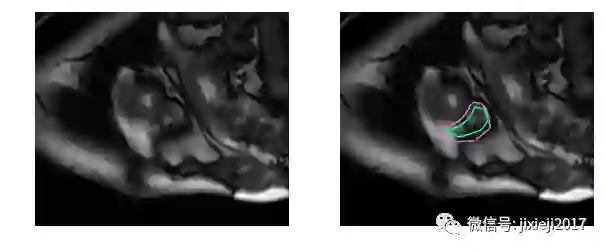

上图的分割较简单。下面是一个比较困难的分割:

分割这些MRI对于未经专门训练的人来说是非常困难的: